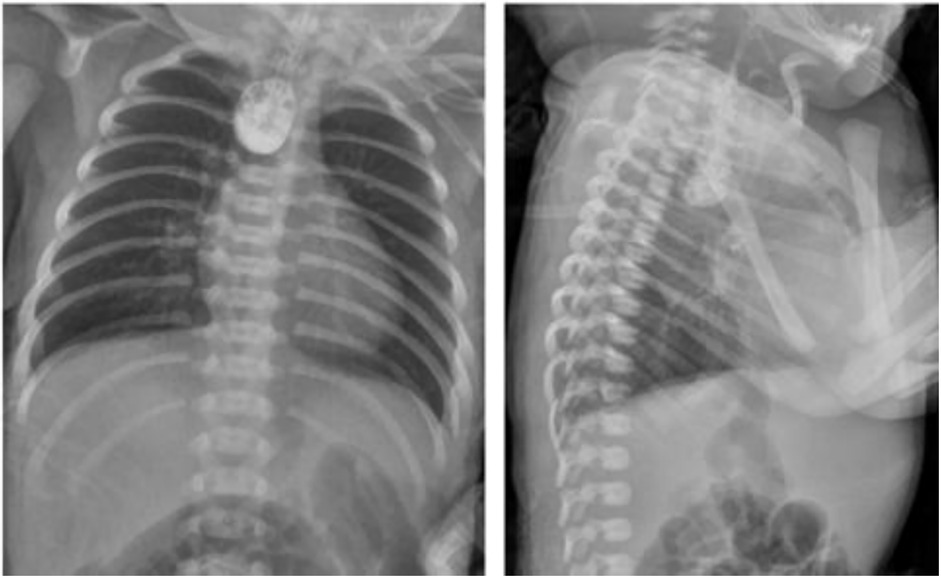

Upper gastrointestinal examination with iodinated water contrast revealed a cystic mass shadow at the level of the lower margin of the third thoracic vertebra (Figure 2). Congenital esophageal atresia (Type C) was suspected based on CT imaging of esophagus. Electron bronchoscopy visualized congenital esophageal atresia with a tracheoesophageal fistula (Figure 3). Craniocerebral ultrasound detected a subventricular cystic lesion on the left side and bilateral dilation of the lateral ventricles. Abdominal color Doppler ultrasound indicated hepatomegaly, with no apparent abnormalities in the gallbladder, pancreas, spleen, or kidneys. Cardiac ultrasound identified an atrial septal defect, patent ductus arteriosus, and patent foramen ovale. Amplitude EEG demonstrated immature sleep-wake cycles (SWCs). Hearing screening using Otoacoustic emissions and the auditory brainstem indicated abnormal results. Fundoscopic examination revealed congenital focal retinal choroidal defects in both eyes (Figure 4). Genetic testing with whole-exome sequencing was positive and identified a de novo heterozygous pathogenic variant in the CHD7 gene, confirmed by Sanger sequencing, with both parents being wild type at this locus (Supplementary Figures S1).

Figure 2. Upper gastrointestinal examination. An appropriate amount of contrast agent was injected through the gastic tube. The upper thoracic segment of the esophagus appeared as a cystic bag shadow, with its lower edge approximately at the level of the lower edge of the third thoracic vertebra. The middle and lower thoracic segments of the esophagus were not visualized.